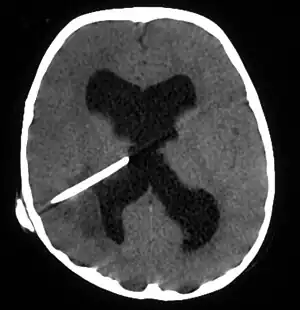

![]() Scanare tomografică a creierului, unde se poate observa abcesul cerebral la un pacient cu un dren ventricular.[1] | |

Diagnosticul este stabilit printr-o examinare tomografică computerizată (CT) (cu contrast) .În faza inițială a inflamației (care se numește cerebrită), leziunea imatură nu are o capsulă și poate fi dificil să o deosebim de alte leziuni sau infarcte ale creierului care ocupă spațiul.În 4-5 zile inflamația și țesutul mortal concomitent al creierului sunt înconjurate cu o capsulă, ceea ce conferă leziunii celebrul aspect care leagă inelul la examen CT cu contrast (deoarece se aplică intravenos materialul de contrast nu poate trece prin capsulă, este colectat în jurul leziunii și arată ca un inel care înconjoară leziunea relativ întunecată. este în toate leziunile creierului care ocupă spațiul) deoarece eliminarea unei anumite porțiuni din lichidul cefalorahidian poate modifica balanța de presiune intracraniană concretă ces și determină deplasarea țesutului creierului prin structuri din craniu (hernie cerebrală).